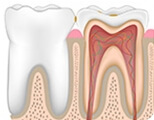

These issues cause tooth painRoot canal needed

Deep Cavity

Pulp Necrosis

Pulp Inflammation

Broken Crown & Root

Periapical Periodontitis

Special Cases

Explore how pulpitis and periapical periodontitis develop

Root canal is the best treatment for pulpitis and periapical periodontitis